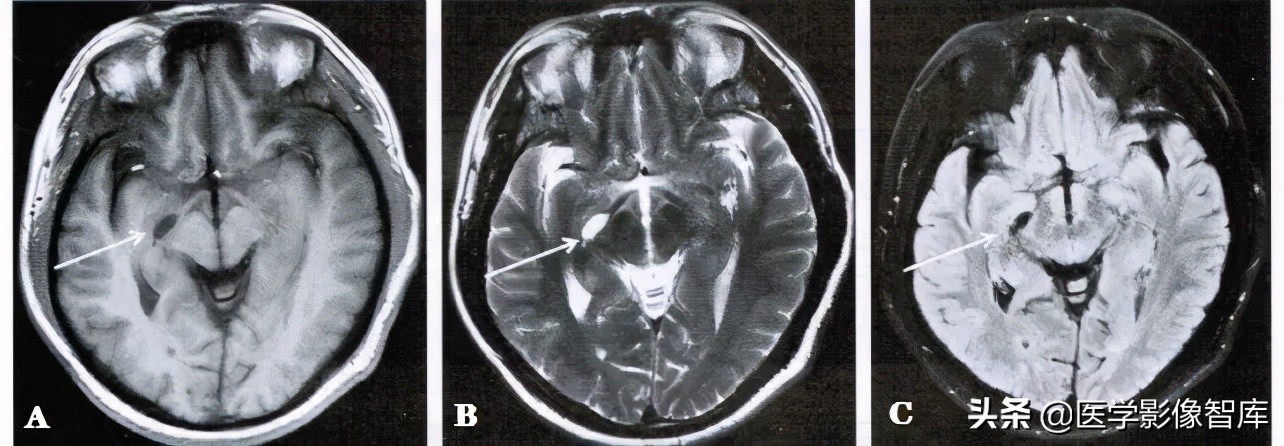

图1 右侧脉络膜裂囊肿

男性,51岁。 A. 轴面T1WI。 B. 轴面T2WI。右侧脑室颞角内侧可见一个冀状长T1、长T2信号影(箭); C. 轴面T2 FLAIR,囊肿在脑脊液抑制像呈低信号(箭)。

因此,脉络膜裂囊肿常沿脉络膜裂和海马沟成角,呈现一个箭头样改变或表现为颞叶内侧的卵圆形、纺锤形囊肿。囊肿长轴沿后上至前下斜行为其特征。在T1WI、T2WI, T2 FIAIR及DWI上,脉络膜裂囊肿的MR信号强度与脑脊液的信号强度基本一致,边界锐利,病灶周围的脑实质无水肿表现(图1、图2)。注射对比剂后增强扫描时囊肿无异常强化。鉴别诊断包括颅内表皮样囊肿、囊性肿瘤、脑软化灶等。